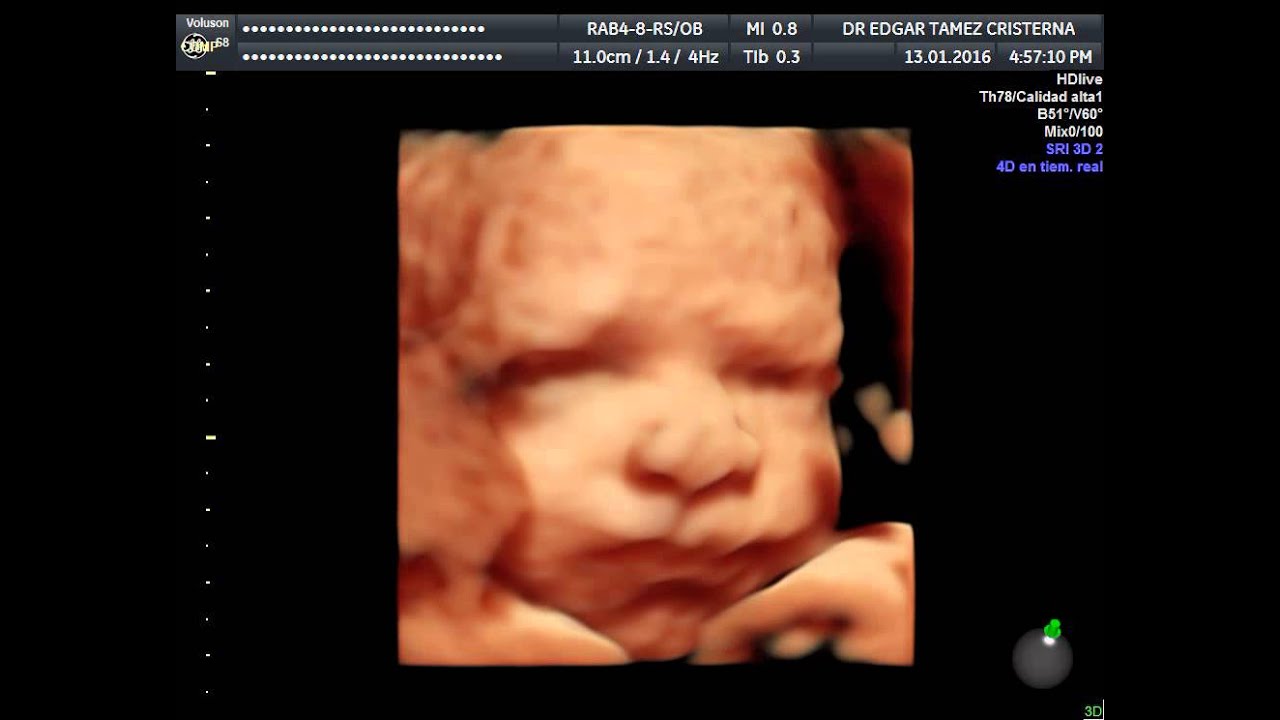

Contamos con el equipo que actualmente ofrece la mejor resolución disponible, tanto para hacer un diagnostico certero, como para que las futuros papás puedan ver una imagen mas realista de su bebe.

Este tipo de ecografía, es la que se hace de manera rutinaria durante el control prenatal, en este estudio se valora el peso del bebe, como esta acomodado, la cantidad de líquido, localización de la placenta, y a partir de las 16 semanas, puede determinarse el sexo fetal con 100% de seguridad No es un estudio muy completo, y por lo que se recomienda realizar el ultrasonido anatomico entre la semana 20-24 para confirmar que el bebe se encuentre bien y descartar la presencia de malformaciones.